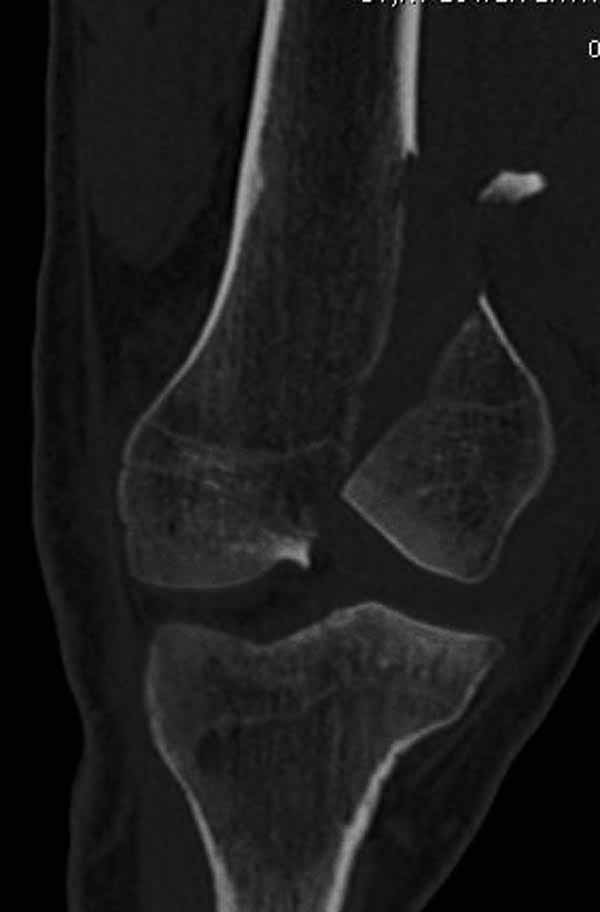

А теперь по поводу лечения перелома. Среди всех чрез/меж-мыщелковых переломов в 38% сопровождются переломом в корональной плоскости, т.е перелом Hoffa. Nork et al, J Orthop Trauma, 87:564, 2005.

По снимку вроде одиночный простой мыщелковый перелом, и такой внутрисуставной перелом не обязательно дистрагировать на скелетном вытяжении, потому что не не нарушается непрерывность колонны с одной стороны. И для таких простых переломов подойдет любой метод: 95 градусная пластина, Lat. Condylar Butress пластина или ретроградный гвоздь. А для особых энтузиастов которые желают антеградную фиксацию, возможно легко найти трохантер у алкоголиков или дистрофиков. А вот у откормленных Макдональдскими гамбургерами? Если поискать у них тоже можно найти, но стоит ли?

У больных как в этом случае, с вовлечением двух мыщелков правильно, что сделали вытяжение до операции. Здесь имеется флексионный компонент на другой стороне, и я бы рекомендовал операцию делать из двух доступов. Сперва фиксировать медиальную колонну custom made пластиной, обычно 1/3 тубулярной пластиной в 4.5 мм, потому что пока производители опаздывают с медиальной пластиной.

Пластину надо устанавливать на апексе перелома, иначе фрагмент начнет сползать. А на второй стороне, если имеется большой одиночный фрагмент тогда проблем не бывает, и их можно собрать компрессирующими винтами. Проблема наступает тогда когда многофрагментраность на латеральной стороне, где надо применить комбинированный метод, иногда несколькими пластинами. Или сменой позиции установки пластины, чтобы максимально прикрыть перелом и создать боковую поддержку.

Здесь пример медиальной пластины и латеральный комбинированный метод (у второго больного старый перелом тибиал плато, леченный где то и когда то)